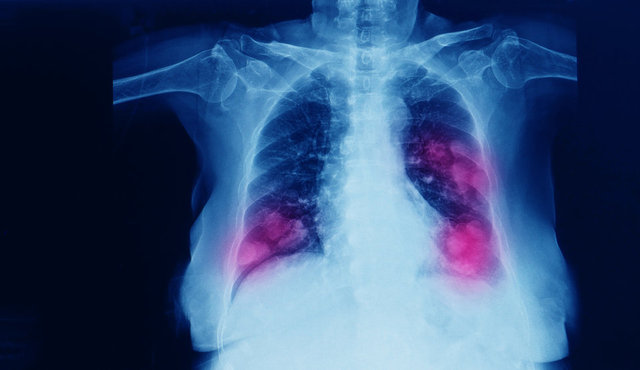

Akciğer kanseri dünyada kanser türleri arasında en sık görülen ve yine en sık ölüme neden olan kanser türü olarak ilk sırada yer alıyor. Tüm kanser ölümlerinin yaklaşık 3’te birinden akciğer kanseri sorumlu. Dünyada her yıl yaklaşık 2,2 milyon kişi sigaranın en önemli risk faktörü olduğu akciğer kanserine yakalanıyor ve 1,6 milyon kişi de bu hastalık nedeniyle hayatını kaybediyor.

Ülkemizde de akciğer kanseri oldukça yaygın. 2020 yılında 40 binin üzerinde yeni akciğer tanısı konulduğu belirtiliyor. Akciğer kanseri, genellikle erken dönemlerinde fazla belirti vermemesi veya en tipik belirtisi olan öksürük geliştiğinde sigara içen kişilerin ‘sigara öksürtüyor’ düşüncesiyle hekime geç başvurmaları nedeniyle sıklıkla ileri evrede teşhis ediliyor. Tedavinin gecikmesi de hastanın hayatını kaybetmesine yol açıyor.